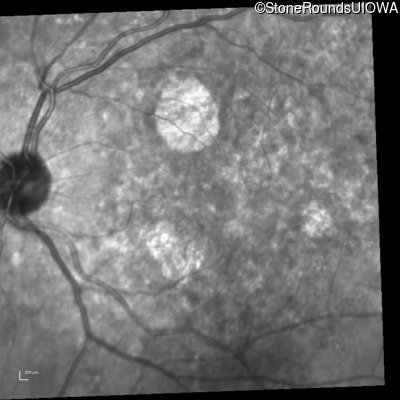

Infrared Fundus Photograph - Right - 20/25 +2

Exemplar